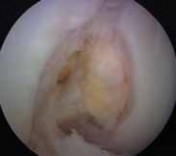

2. The tip of the guide is placed in the posteromedial aspect of the native ACL footprint. The difficulty is that the native ACL footprint is no longer visible. Therefore, we place the guidewire so that it penetrates the joint 6 to 7 mm anterior to the PCL and in a line that intersects the posterior aspect of the anterior horn insertion of the lateral meniscus (

TECH FIG 2A

).

TECH FIG 2 • A. Placement of the tibial tunnel guidewire just anterior to the native posterior cruciate ligament (PCL). B. Appearance of the revision tibial tunnel using the arthroscope to inspect for compromise from the index procedure. C. After reaming the femoral tunnel to a depth of 10 mm, the tunnel is inspected to ensure the posterior wall is intact.

2. The tunnel is inspected with the arthroscope for wall compromise from the previous tunnel (

TECH FIG 2B

). This can be performed by placing the arthroscope up the tibial tunnel.

2. It is then brought back into the notch so that the back wall can be inspected (

TECH FIG 2C